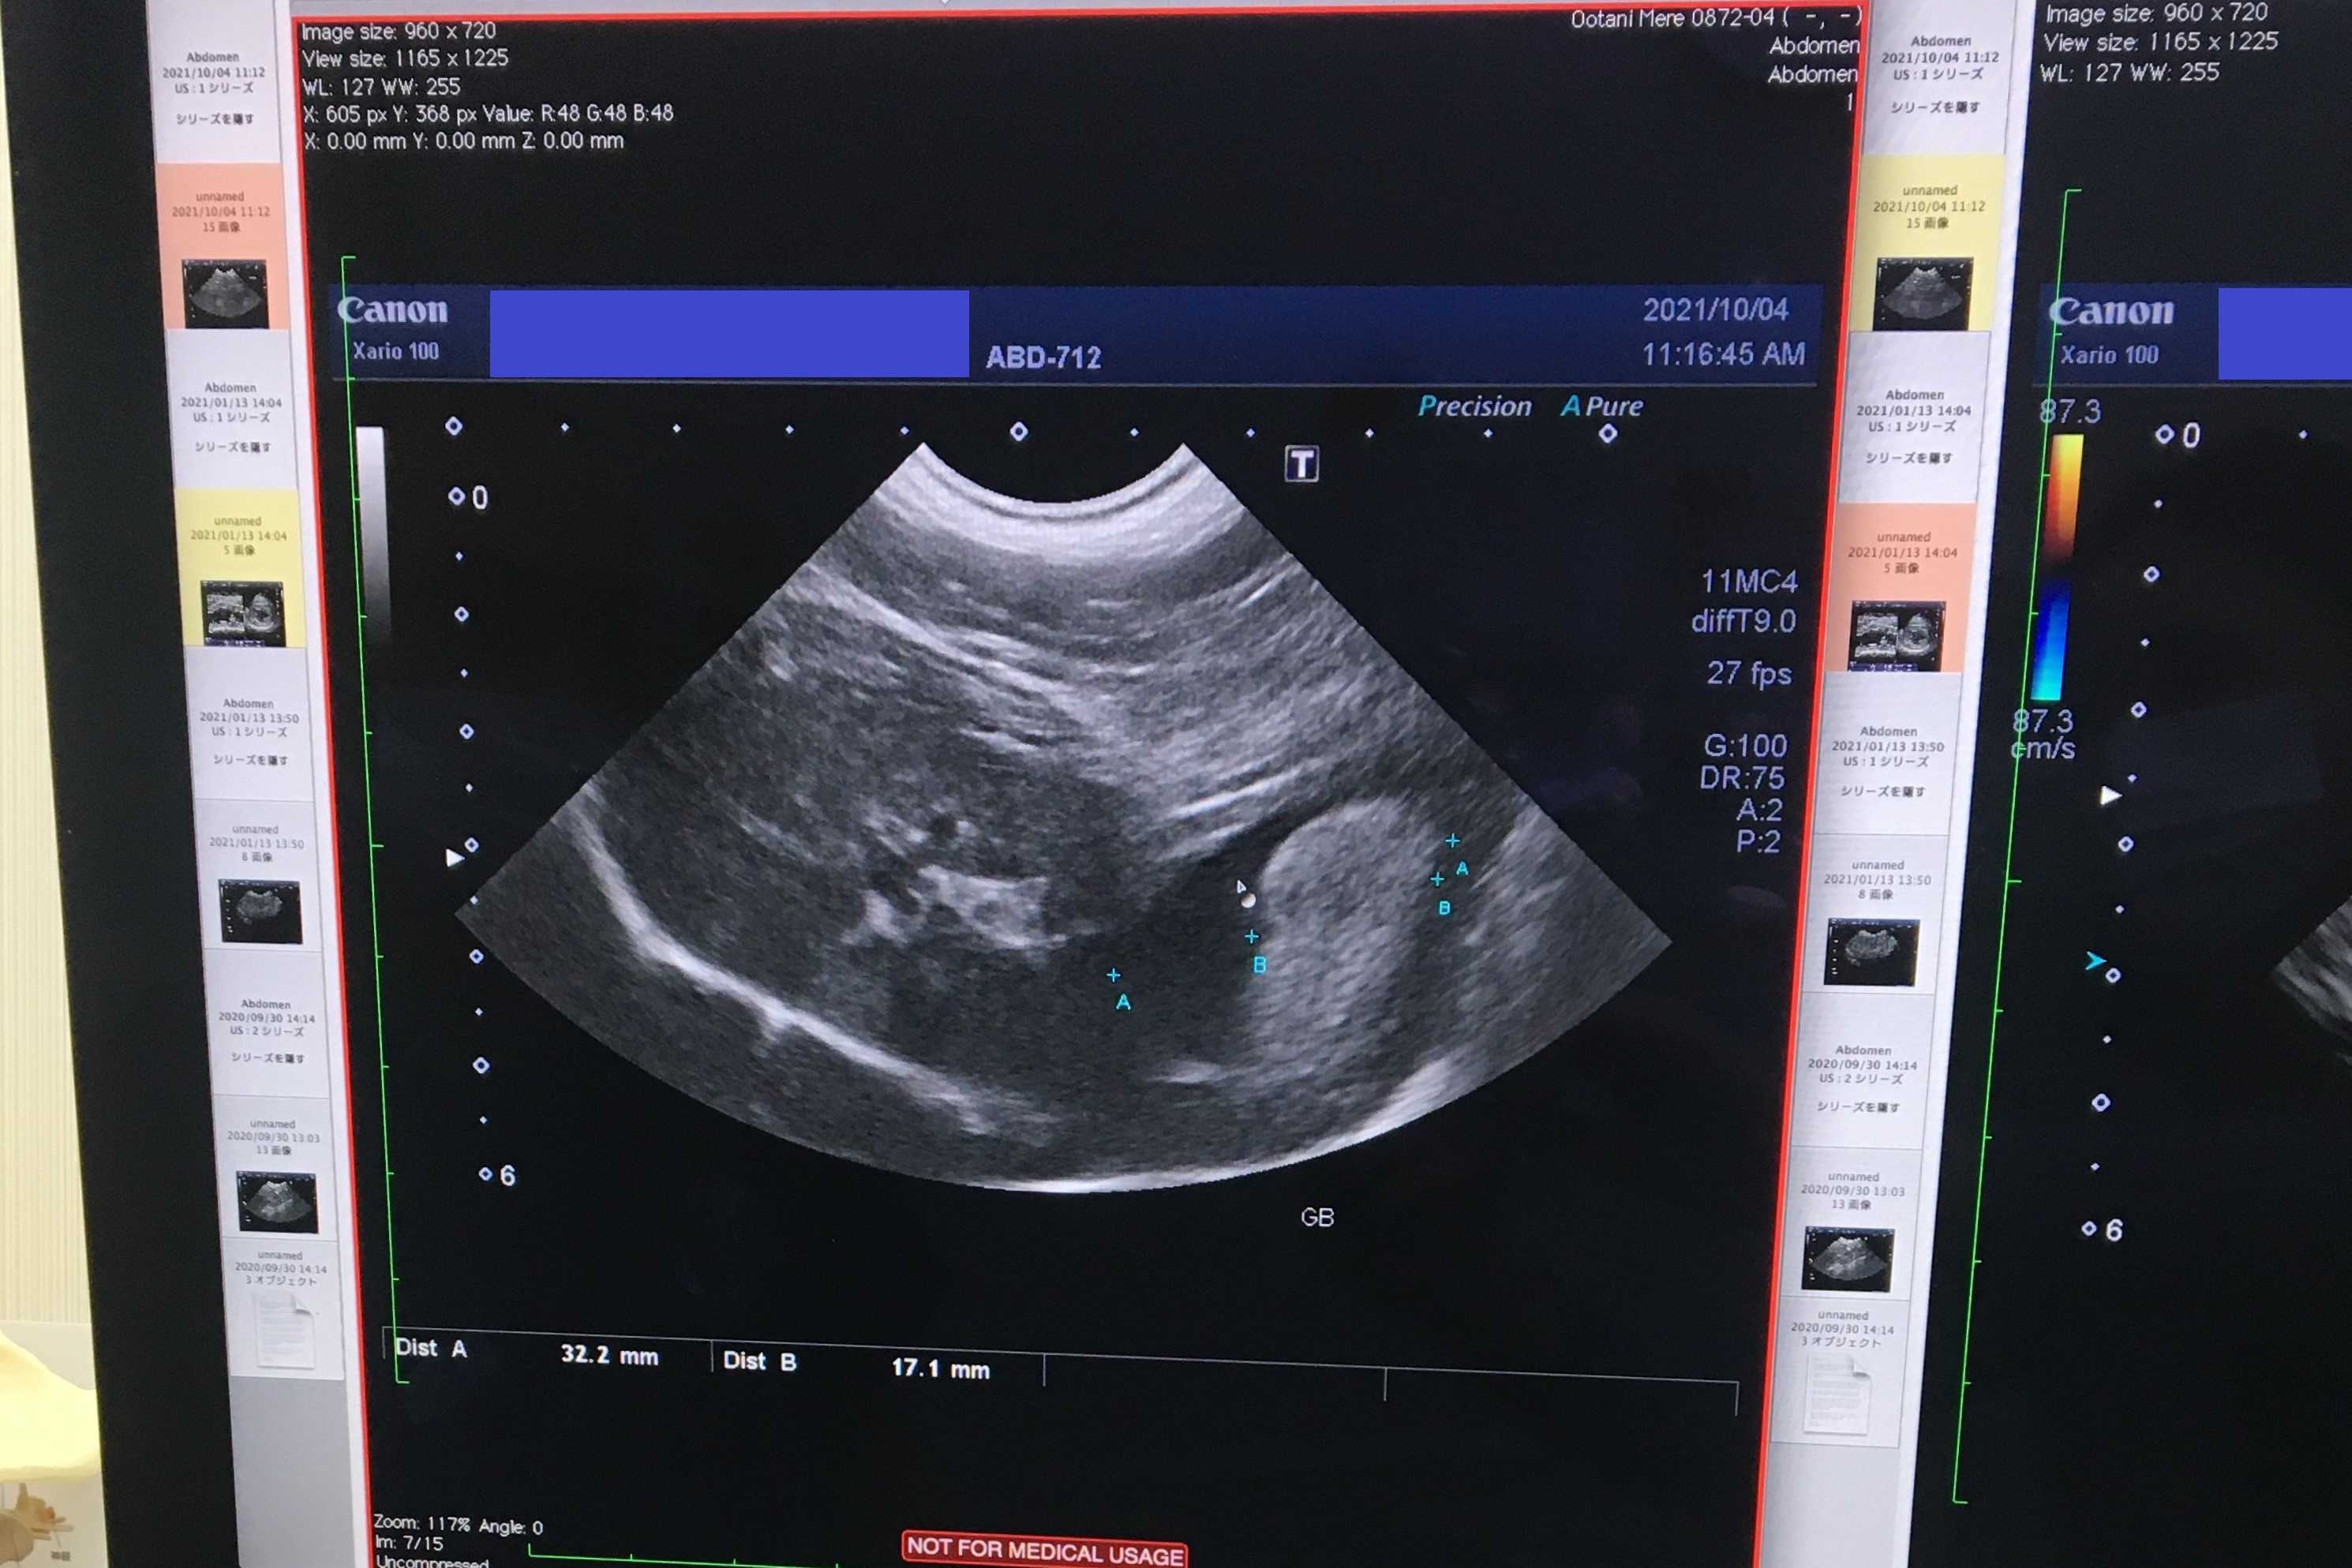

こちら胆嚢の画像なんですが

若干胆汁が溜まっているかなと

結構たくさん溜まっているように見えるのですが

これは一番太い部分を選んで撮影したからです

実際は胆汁は流れていますので

血液検査の結果を見て

考えていきましょう